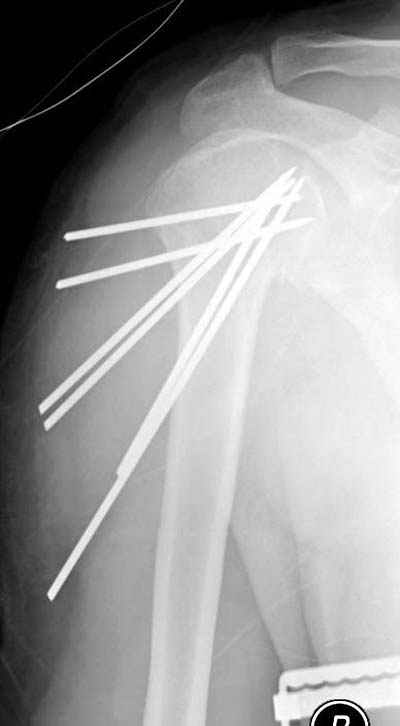

Спасибо за участие в дискуссии -перелом шейки плеча, для себя я прояснил многие технические моменты...

Посылаю послеоперационные Рг граммы.

Поздравляю, получилось просто замечательно. Если можно, расскажи чуть подробнее, как делали - как вправляли, как вводили спицы, поворачивали ли их?

Спасибо за поздравления:-))

Я и сам доволен результатом. В предпоследнем письме я кратко описал ход операции - закрыто репонировать не удалось( 2 недели с момента травмы и 1 неделя после неудачной репозиции) после удаления пучков спиц, пришлось сделать - 2см разрез на уровне перелома и с помощью периостального элеватора (золотое правило механики) *одеть* головку на дистальный отломок.

Спицы проводил через старые отверстия, вращая пучок импактором- направителем при его введении в головку.